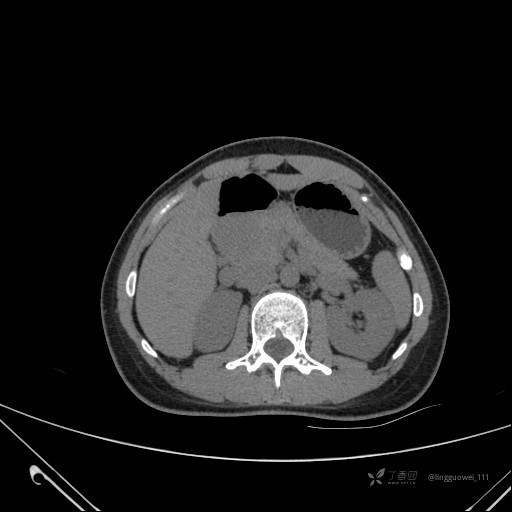

患者性别:女

患者年龄:28岁

主诉:体检发现胰腺病变,行 CT检查。

平扫: